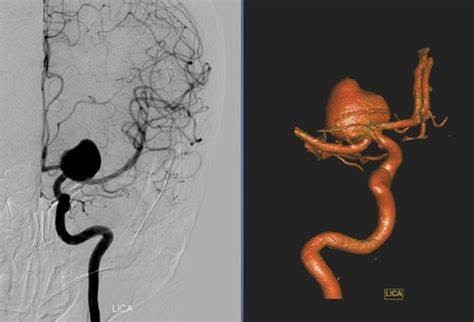

要想知道腦內(nèi)是否有動脈瘤,早期篩查很重要。目前篩查的方法主要有兩種,一種為計算機(jī)輔助斷層掃描血管造影(CTA),可清晰顯示腦血管的情況;另一種為磁共振血管造影(MRA),也可將血管顯像以發(fā)現(xiàn)腦動脈瘤。這兩種方法均能合適檢查出大多數(shù)超過3-5毫米的腦動脈瘤。建議40-50歲人群,每年體檢時可以進(jìn)行腦動脈瘤篩查。另外,如果家庭成員中有人患腦動脈瘤,其他人較好也在醫(yī)生指導(dǎo)下做腦血管造影等檢查。

目前,腦動脈瘤的治療已經(jīng)成熟了,目前常用的兩種方法,一種是開顱夾閉動脈瘤;另一種是微創(chuàng)的介入栓塞動脈瘤,如果手術(shù)順利,患者可以不留任何后遺癥。腦動脈瘤夾閉術(shù)被證明是合適的。一項國外研究報告表明,腦動脈瘤夾閉術(shù)是對動脈瘤的干預(yù)手段中研究結(jié)果比較好的一種,已經(jīng)被證明可以完全消除90%的動脈瘤。能合適好轉(zhuǎn)腦動脈瘤患者的預(yù)后生活,降低動脈瘤再次出血的風(fēng)險,一般來說手術(shù)切除的動脈瘤不會復(fù)發(fā)。